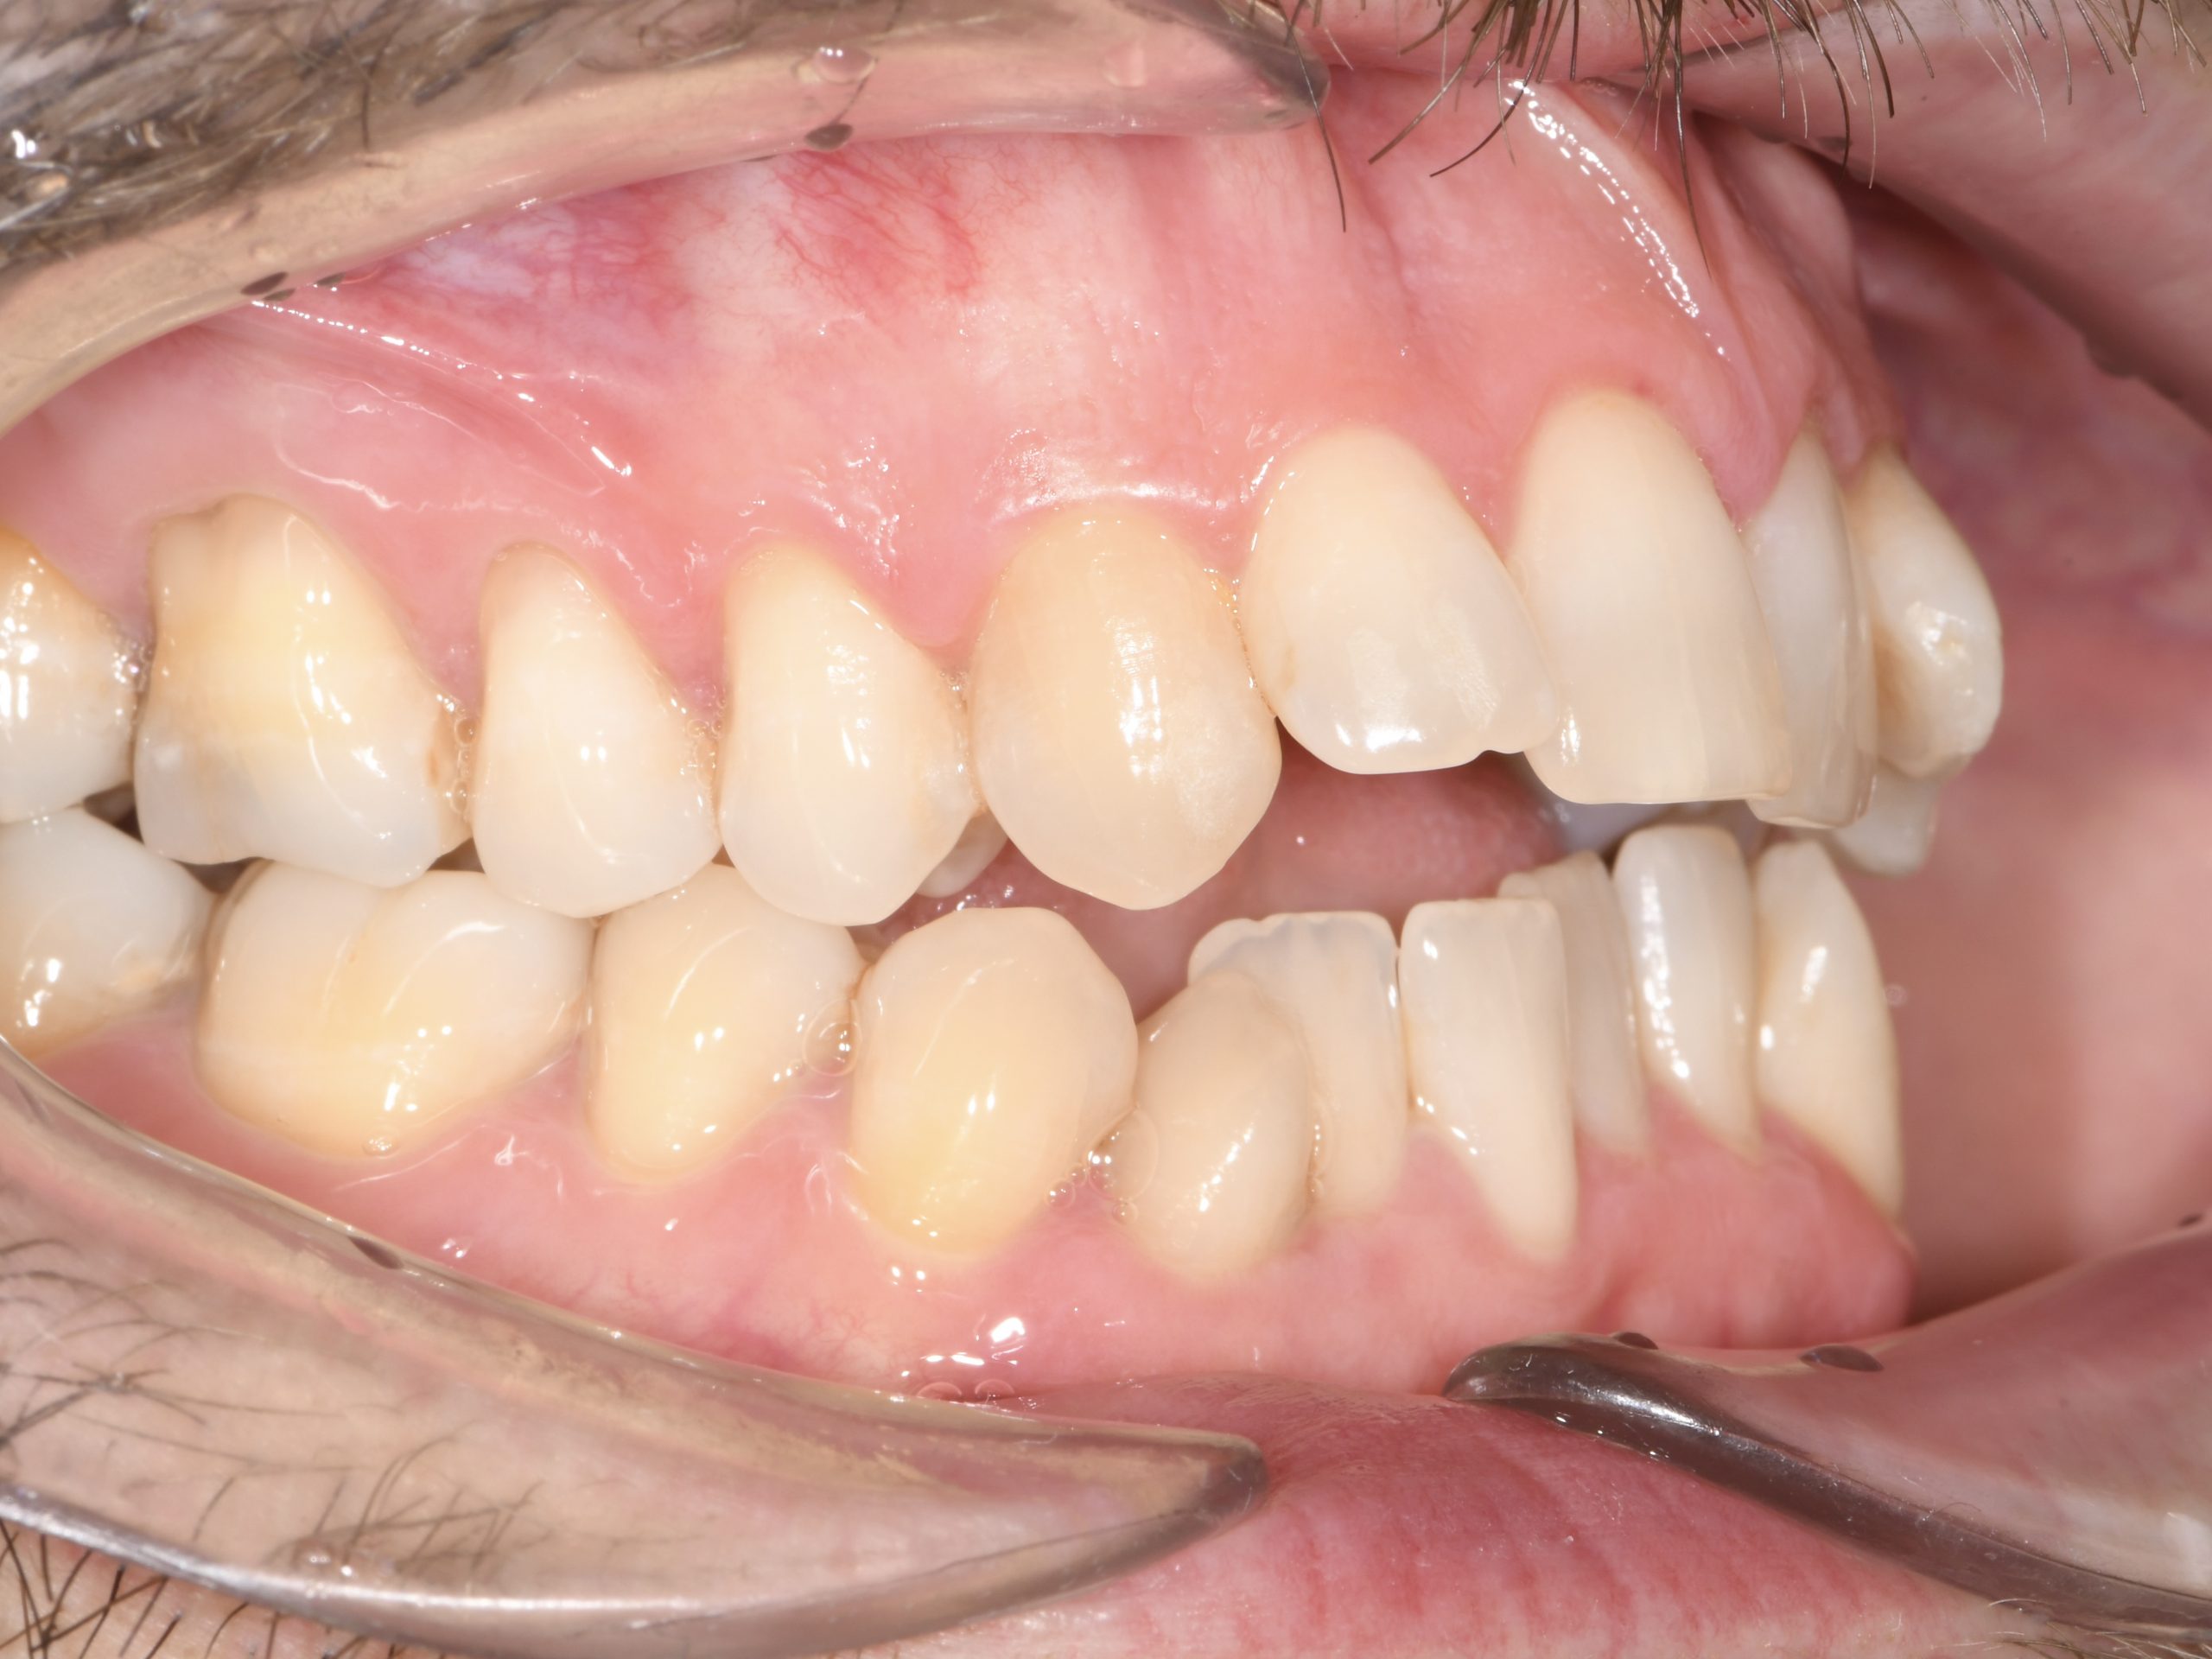

Az elmúlt évekből rengeteg szakmai referenciát tudnánk bemutatni, amelyek különböző fogszabályozási problémákat oldottak meg. Válogatva a több száz esetből, ezen az oldalon olyan képeket, információkat igyekeztünk bemutatni, amelyeknek a segítségével a jövőbeni pácienseinknek azt tudjuk üzenni: A Te fogsorod is lehet gyönyörű!

(Képeket a Pácienseink külön írásos beleegyezésével mutatjuk be!)